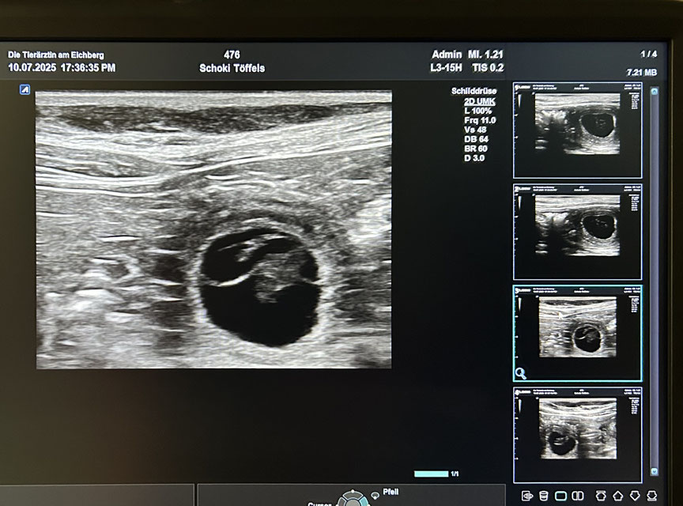

10.07.2025

Wir waren am Donnerstagabend beim Ultraschall und was soll ich sagen ... Schoklinde ist trächtig!! Die Fruchtblasen sind schön mit Wasser gefüllt, die kleinen Embryonen konnte man schon gut erkennen, auch, wenn sie noch nicht wie Hunde ausgesehen haben 😊 Aber die Herzchen haben geschlagen 💓 Wir sind voller Freude. Nun gehen wir in Vorbereitung für unseren D-Wurf. Wir sind einfach HAPPY 🤸🏼🎉🍀 Drückt uns die Daumen.